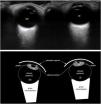

La ecografía ocular se debe realizar con el paciente en decúbito supino y con los párpados cerrados. Se obtienen al menos 2 planos ortogonales para visualizar el globo ocular y el nervio óptico (Ort). También se puede obtener una proyección oblicua (Obl) para poner de manifiesto el iris y la pupila, y valorar el reflejo fotomotor. Se aplica un transductor lineal de alta frecuencia (5-10MHz) sobre el párpado superior y se identifica, en un plano coronal a nivel del cristalino, el iris como una estructura que rodea a una zona circular anecoica correspondiente a la pupila. En las imágenes superiores se visualizan ambos ojos en miosis tras la estimulación lumínica transpalpebral. En las figuras inferiores se esquematizan cada una de las imágenes superiores. Con el objeto de minimizar los índices térmicos y mecánicos, se debe seguir la filosofía As Low As Reasonably Achievable (ALARA). OD: ojo derecho; OI: ojo izquierdo.

En las imágenes superiores (Obl) se observa el ojo derecho en midriasis ante la privación lumínica directa y consensual; y el ojo izquierdo, en miosis en situaciones similares, lo que pone de manifiesto la ausencia del reflejo fotomotor, sugestivo de inflamación de la cámara anterior (uveítis anterior). En las figuras inferiores se esquematizan cada una de las imágenes superiores.